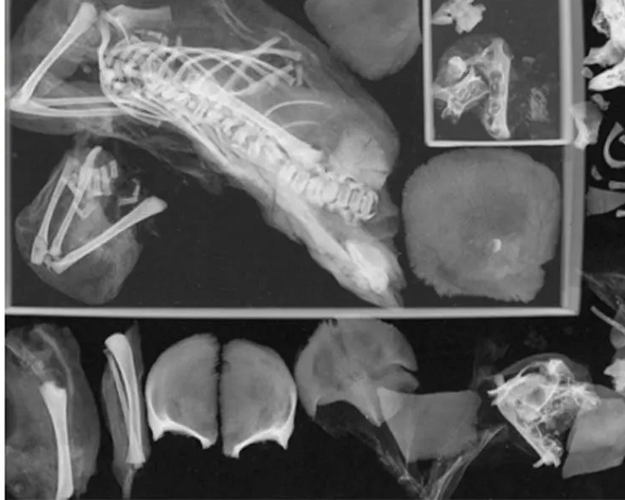

Cách đây không lâu, một xác ướp thiếu nữ Ai Cập khoảng 14-17 tuổi, sống vào thời kỳ Hậu nguyên Ai Cập cổ đại (khoảng giữa năm 712 đến 332 TCN) đã làm kinh ngạc những nhà khoa học khi phát hiện bí ẩn độc đáo bên trong cơ thể của cô.

Ban đầu, các nhà nghiên cứu kết luận rằng thiếu nữ đã qua đời do một ca sinh khó, với hộp sọ của thai nhi mắc kẹt trong ống sinh. Tuy nhiên, sau nhiều thập kỷ, nhóm nghiên cứu mới sử dụng phương tiện chẩn đoán hình ảnh hiện đại và phát hiện ra bí ẩn thứ hai.

Bí ẩn này là một bào thai thứ hai, được giữ nguyên thông qua quá trình ướp cẩn thận trong cơ thể của người mẹ. Vị trí bí ẩn này có thể là do cơ hoành và các cấu trúc mềm khác bị hư hại sau khi thiếu nữ qua đời, khiến xác ướp thai nhi thứ hai không còn nằm nguyên trong bụng.

Phát hiện này góp phần giải mã về cuộc sống và cái chết trong thời cổ đại Ai Cập, đặc biệt còn làm nổi bật sự khắc nghiệt của các cuộc vượt cạn thời kỳ cổ đại, phụ nữ thường mang thai và sinh nở khi còn là thiếu nữ, khi cơ thể chưa phát triển đầy đủ, gây ra nhiều rủi ro.